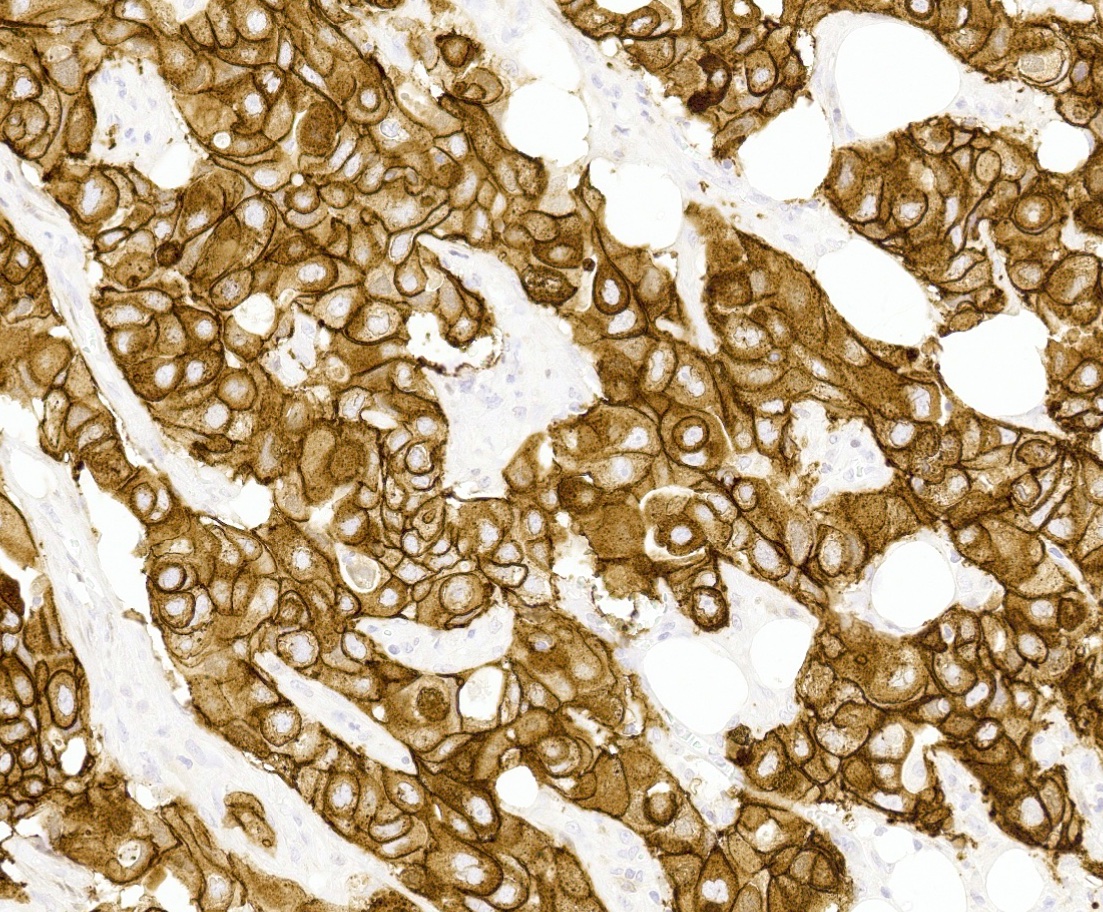

- HER2 enriched

- Predominantly IDC, NST of high histological grade

- Tumor cells frequently have pleomorphic nuclei and more abundant eosinophilic cytoplasm than triple negative cancers

- Ki67 proliferative rate is high (20 - 60%)

- Frequently associated with high grade comedo ductal carcinoma in situ

- HER2 enriched